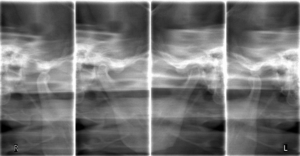

パントモCT装置

使用装置:モリタ社製ベラビューX800

2021年7月に歯科口腔外科系の撮影を行うパントモCT装置が新たに導入されました。

この装置では、2次元的に歯や顎の撮影を行うオルソパントモ撮影や顎関節撮影に加え、3次元で立体的に歯や病変を描出できるコーンビームCT撮影の機能も搭載されました。そのため従来の装置と比較して、より画質の良い、診断に有用な優れた画像検査が可能となります。

| オルソパントモ画像 | 顎関節断層画像 |